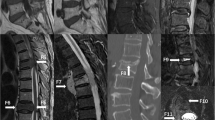

This retrospective study included patients within 6 weeks of back pain (non-traumatic) who underwent MRI and were diagnosed with benign and malignant indistinguishable VCFs. The two cohorts were retrospectively recruited from the Affiliated Hospital of Qingdao University (QUH) and Qinghai Red Cross Hospital (QRCH). Three hundred seventy-six participants from QUH were divided into the training (n = 263) and validation (n = 113) cohort based on the date of MRI examination. One hundred three participants from QRCH were used to evaluate the external generalizability of our prediction models. A total of 1045 radiomic features were extracted from each region of interest (ROI) and used to establish the models. The prediction models were established based on 7 different classifiers.